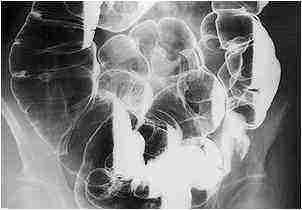

- Ирригоскопия представляет собой диагностическую процедуру, при которой в кишечник вводится специальное вещество. Это позволяет получить четкое изображение на рентгене и установить причину кровотечения из ануса.